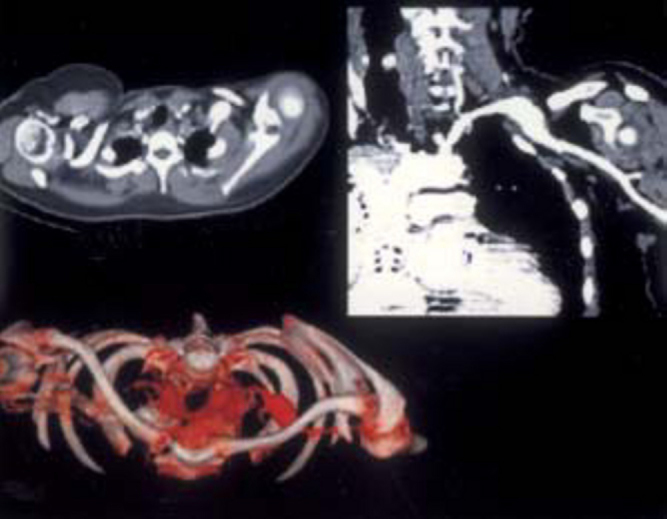

Fig. 2A.

Subclavian artery pseudoaneurysm. Clockwise from left are a) Axial CT section showing dilatation of subclavian artery, b) Coronal MPR shows the aneurysm tapering into the axillary artery with distal run off, c) 3D virtual reality (VR) technique depicts the complex relationship between pseudoaneurysm, cervical rib and left clavicle.

Fig. 2B.

Stent graft treatment of subclavian artery pseudoaneurysm. At left are DSA images showing an increase in pseudoaneurysm size. At right a color doppler image shows turbulence within pseudoaneurysm. DSA images display flow across the stent graft and isolation of pseudoaneurysm with adequate distal run off.